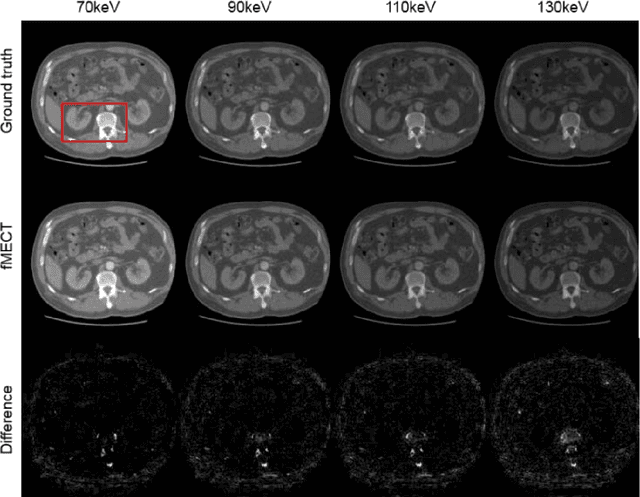

Abstract:Energy-resolving computed tomography (ErCT) has the ability to acquire energy-dependent measurements simultaneously and quantitative material information with improved contrast-to-noise ratio. Meanwhile, ErCT imaging system is usually equipped with an advanced photon counting detector, which is expensive and technically complex. Therefore, clinical ErCT scanners are not yet commercially available, and they are in various stage of completion. This makes the researchers less accessible to the ErCT images. In this work, we investigate to produce ErCT images directly from existing energy-integrating CT (EiCT) images via deep neural network. Specifically, different from other networks that produce ErCT images at one specific energy, this model employs a unified generative adversarial network (uGAN) to concurrently train EiCT datasets and ErCT datasets with different energies and then performs image-to-image translation from existing EiCT images to multiple ErCT image outputs at various energy bins. In this study, the present uGAN generates ErCT images at 70keV, 90keV, 110keV, and 130keV simultaneously from EiCT images at140kVp. We evaluate the present uGAN model on a set of over 1380 CT image slices and show that the present uGAN model can produce promising ErCT estimation results compared with the ground truth qualitatively and quantitatively.